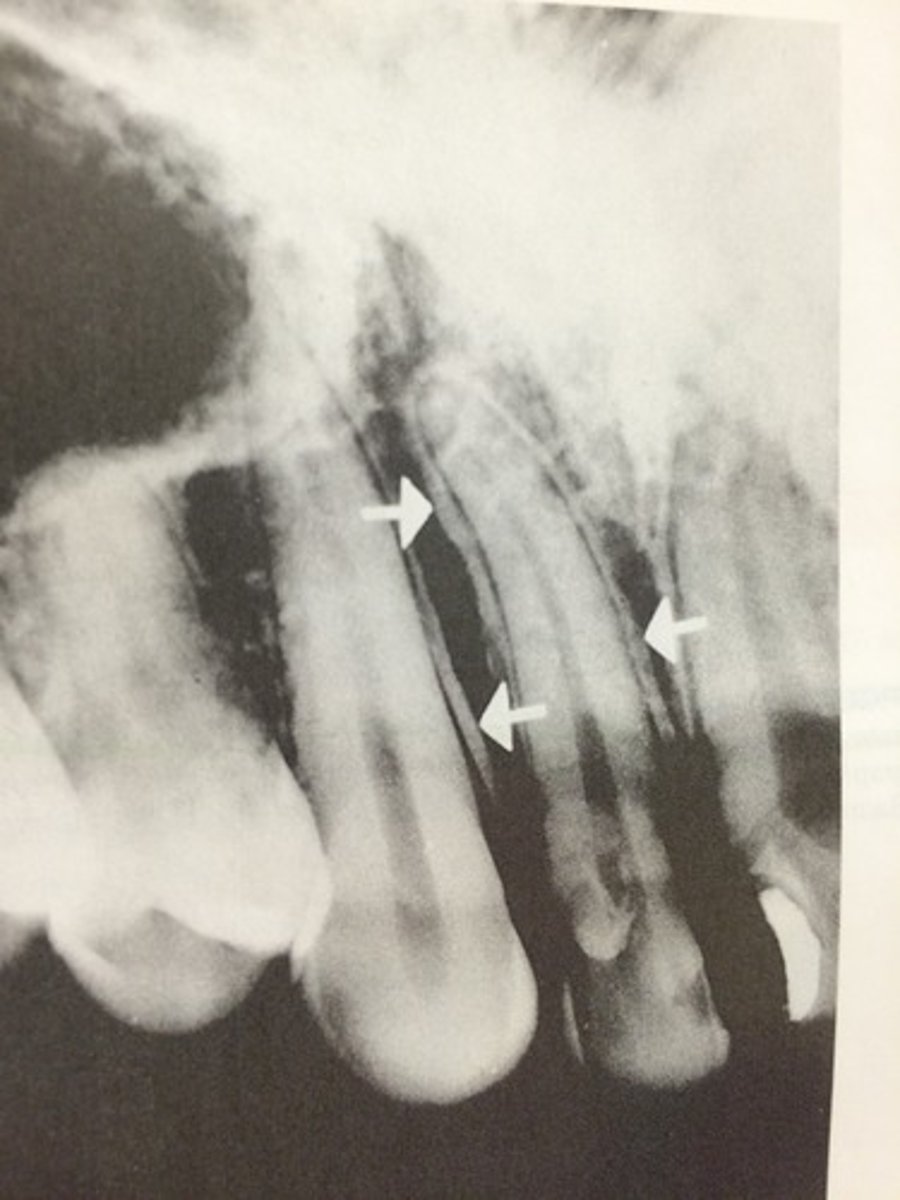

What is sequestration in chronic osteomyelitis?

Necrotic bony islands

What develops during chronic osteomyelitis?

Sinus tract